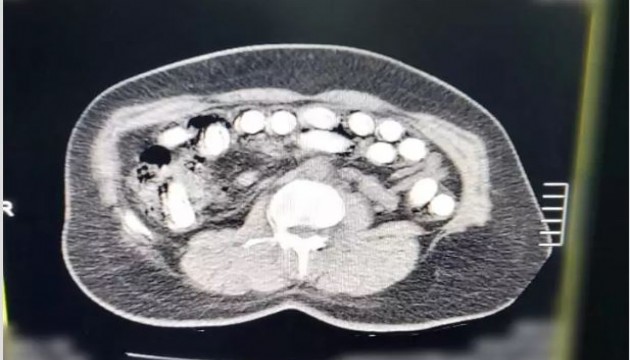

Edinilen bilgiye göre, Kayseri İl Emniyet Müdürlüğü Narkotik Suçlarla Mücadele Şube Müdürlüğü ekipleri tarafından uyuşturucu madde ticareti yaptığı değerlendirilen şahıslarla ilgili çalışma yapıldı. Yapılan çalışmalar neticesinde yakalanan A.G.’nin (36) yapılan iç beden muayenesinde mide ve bağırsak bölümünde 88 kapsül halinde toplam 974.52 gram uyuşturucu madde tespit edildi. Öte yandan, A.A.’nın (34) yapılan üst aramasında; 2,7 gram uyuşturucu ve 76 adet narkotik hap ele geçirildi.